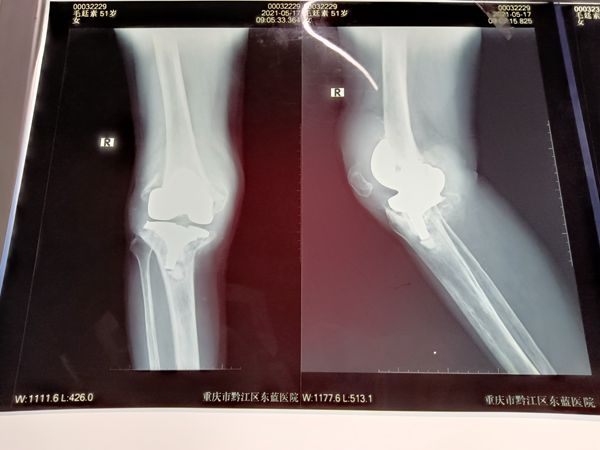

術前

入院后,該院骨科主任冉祥通過仔細查體并結合X線檢查,診斷考慮趙阿姨因假關節周圍骨折未能及時救治導致關節假體松動,且由于時間長導致骨質破壞嚴重,加上假體松動磨損,骨質缺損大,需要手術翻修。

冉祥介紹,患者股骨端及脛骨端缺損明顯,原假體已經明顯松動移位,伴隨的是嚴重的骨量丟失,就好像一棟房子地基周圍的土質流失了,地基也就不穩了。